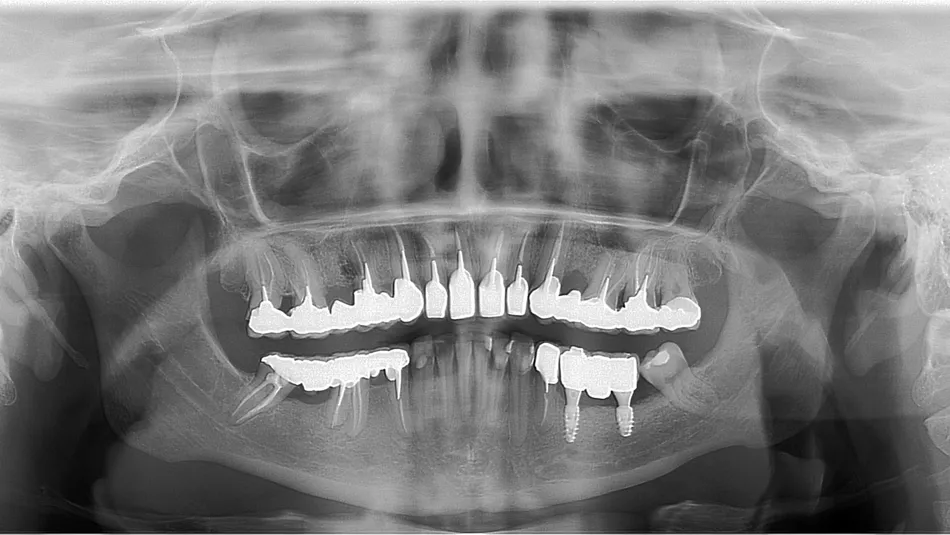

A 38-year-old patient presents for oral surgery consultation referred by her dentist for the replacement of teeth 35 and 36. The patient is in good health, a smoker at the time of the consultation, with the will to quit. The initial CT scan shows significant bone atrophy in all three spatial directions (height 4 mm above the mental foramen, Cawood 5) with a low well-rounded ridge presentation ​[1]​. The prosthetic project was to create two implant-supported crowns at sites 35 and 36. To regenerate the bone at the site, we opted for an autogenous bone graft protocol as described by Professor F. Khoury. The aim is to reconstruct the bone volume of the site in the horizontal and vertical directions with a high tolerance ​[2]​​.

1. Cawood 5 mandibular atrophy in the posterior mandibular sector with absence of teeth 35 36.

9. Panoramic control 2 years after the implants were put into service.